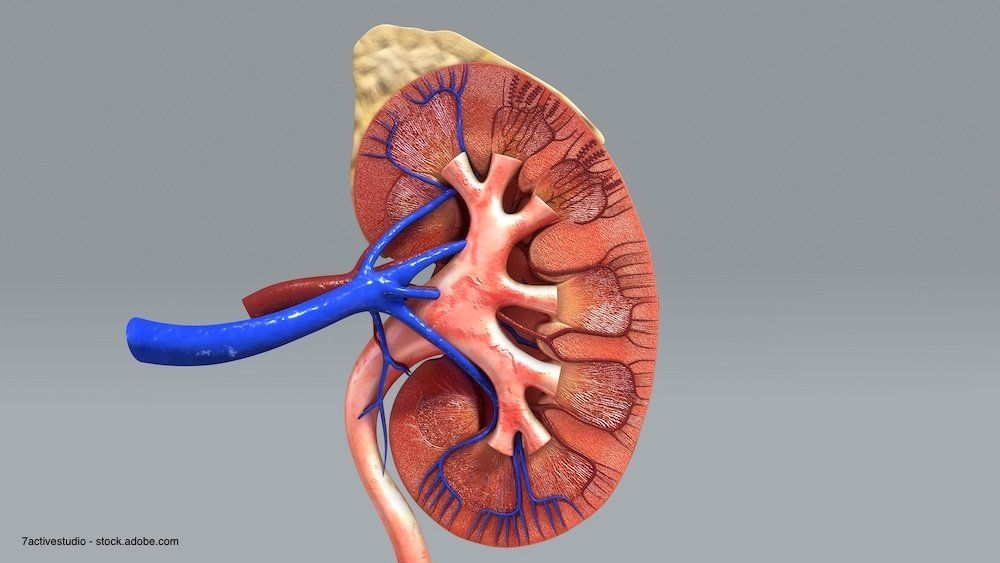

Super-mini percutaneous nephrolithotomy may have some advantages over retrograde intrarenal surgery when treating 1- to 2-cm lower pole renal calculi, according to a comparative study.

Researchers who are investigating burst-wave lithotripsy, a potential alternative treatment for kidney stones, report that magnetic resonance imaging and ultrasound scans hold promise as tools to help scientists analyze related kidney injuries.